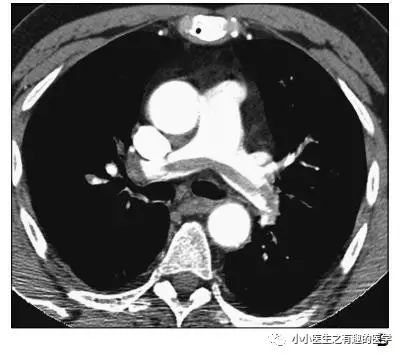

作者单位:Department of Radiology, Thoracic Imaging Section, San Francisco General Hospital(旧金山总医院)。

如图,高密度影的那一条。

不怕,有增强CT证实。

是不是很有趣。